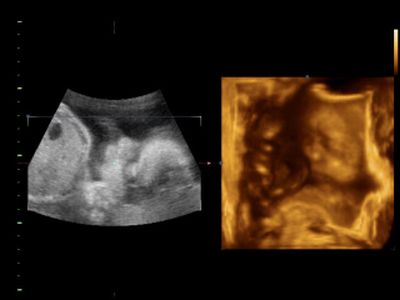

Amúgy a lába Gergőnek is rövid volt az UH szerint, aztán mégsem. Jól megijesztettek engem is, mondjuk nálunk az volt a "jó", hogy előtte már megcsináltattuk a magzatvíz mintavételt és minden ok volt, ezért nem voltam annyira ideges a végén, de azért nem esett jól. Remélem nálatok is csak rosszul látják. Majd rögtön megkeresem a méreteket.